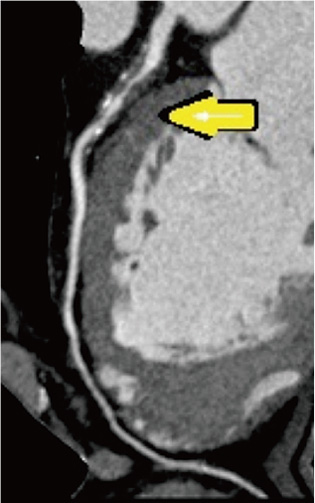

2011年、早歩き中に胸が痛くなったとの訴えがありました。運動負荷テストでST低下を認めたため、CTA(造影CTによる冠動脈の検査)を施行。冠動脈の左前下降枝近位部に不安定な高度狭窄病変の所見でした(

黄色矢印)。K病院にてステント治療を行い、症状は消失しました。82歳になった今も、元気に通院されています。